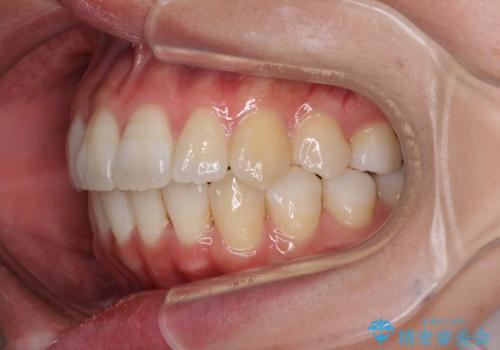

- 上下の歯の前後関係が乱れ、歯に負担がかかるとのことで来院された患者様です。

下顎が右左側に変位しているため、左側奥歯の咬み合わせが上下反対の関係となっていました。

また、上下ともに歯列が狭窄しており、奥歯以外にも反対咬合が認められました。

骨格的な問題を抱えた左奥以外は比較的早く咬み合わせが改善しましたが、左奥はどこで咬み合えば良いのか分からず、大変不便な思いをされていました。

ゴムかけにご協力いただき、最終的には反対咬合を改善することができ、患者様には大変満足していただきました。